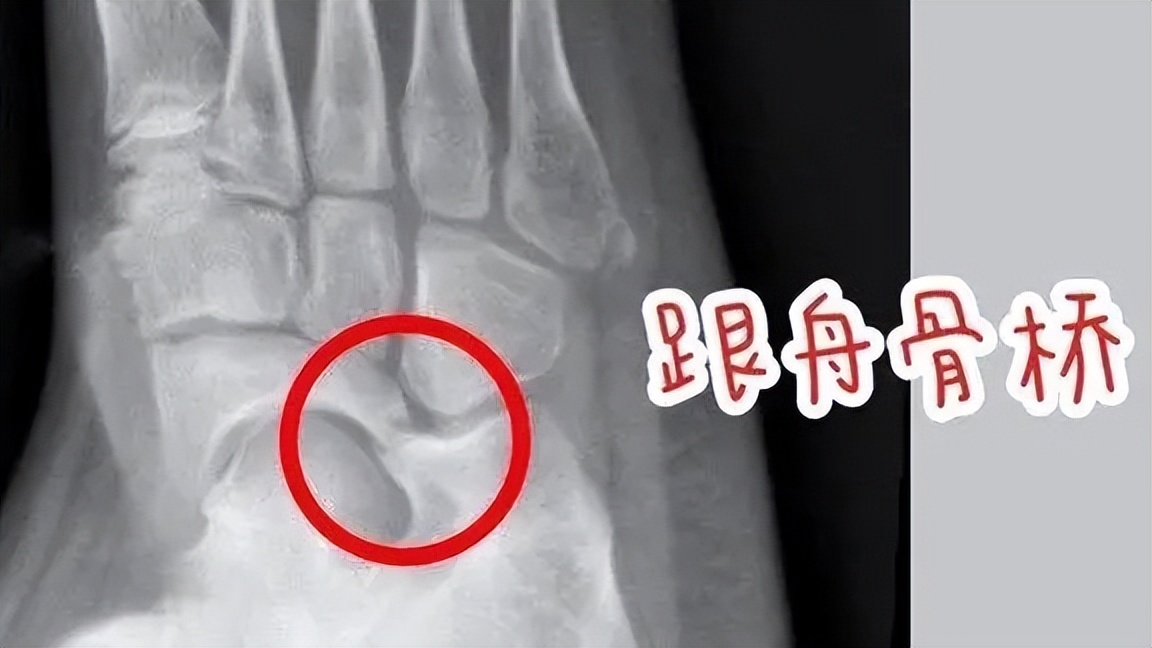

跗骨联合(骨桥):跗骨联合指的是两块或者两块以上跗骨之间出现了不该有的连接,对它们之间的活动造成限制,过去俗称为“骨桥”。学龄期,足部的骨骼逐渐成形,跗骨联合的部位也因为骨化变得僵硬起来,从而产生疼痛、经常扭伤、容易疲劳等表现。

跟舟骨桥